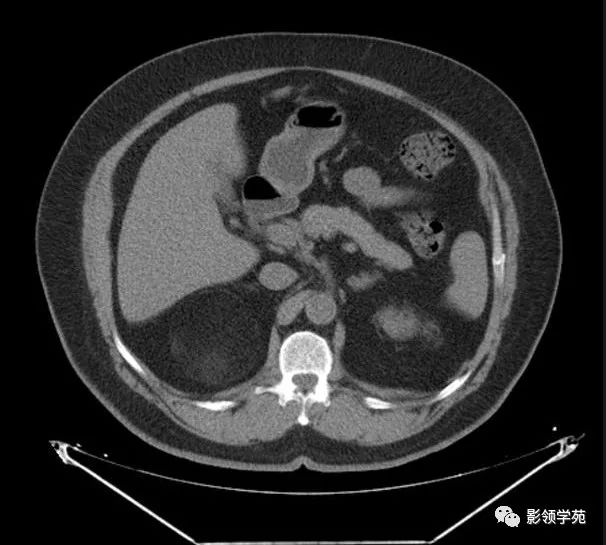

核磁诊断:左侧肾上腺髓样脂肪瘤可能,肿瘤大小约10cm,位于脾门及胰体

图片尺寸2296x1910